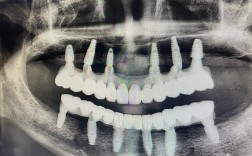

(图片来源网络,侵删)- 医院等级: 三甲医院、大型连锁口腔机构、高端私立诊所通常价格较高,但设备、技术、消毒、服务更有保障。